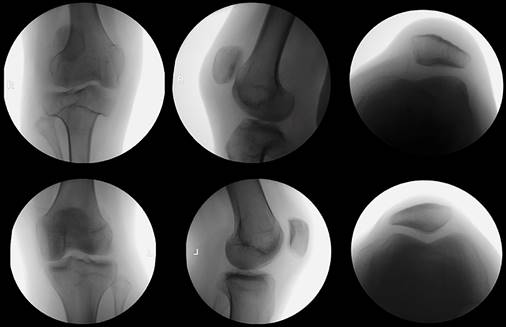

Physical examination revealed knee range of motion from 0o to 90o, altered patellar tracking, quadriceps atrophy, a positive «J» sign, and a highly positive apprehension test. Radiographic examination revealed a high-riding patella with a Caton-Deschamps index of 1.38 (normal range 0.6-1.3) and lateral displacement (Figure 1). Trochlear and tibial plateau dysplasia were observed (Figure 2). Magnetic resonance imaging revealed severe trochlear dysplasia (Dejour type C) and a laterally displaced and tilted patella. The tibial tuberosity-trochlear groove distance (TT-TG) was 18.7 mm on magnetic resonance imaging (MRI).9 The study also indicated elongation of the MPFL and absence of cartilaginous damage. After failed conservative management, involving adaptive adjustments to the prosthesis, a decision was made with the patient to undergo patellofemoral stabilization.

Figure 2: Comparative radiographs in the amputee leg and normal knee (upper and lower images, respectively).